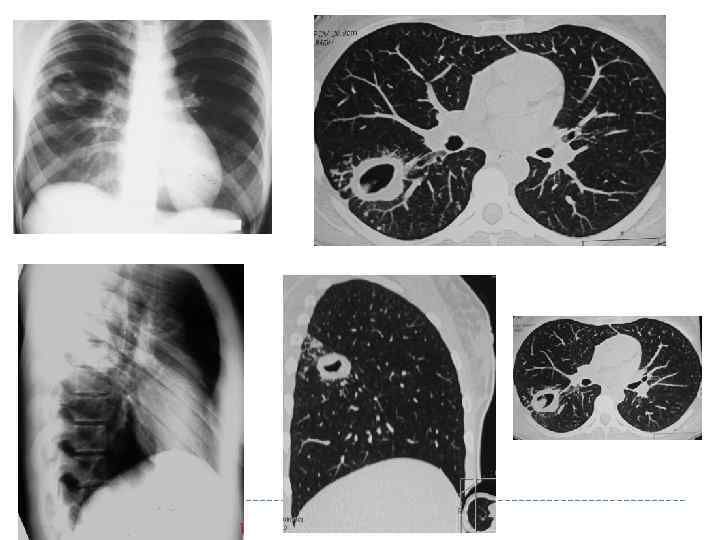

КАВЕРНОЗНЫЙ ТУБЕРКУЛЕЗ ЛЕГКИХ Характеризуется наличием сформированной каверны круглой (овальной) формы без выраженных перифокальных и фиброзных изменений в окружающей легочной ткани. Этой форме туберкулеза соответствует «синдром сформированной свежей (эластической) полости» .

КАВЕРНОЗНЫЙ ТУБЕРКУЛЕЗ ЛЕГКИХ Характеризуется наличием сформированной каверны круглой (овальной) формы без выраженных перифокальных и фиброзных изменений в окружающей легочной ткани. Этой форме туберкулеза соответствует «синдром сформированной свежей (эластической) полости» .